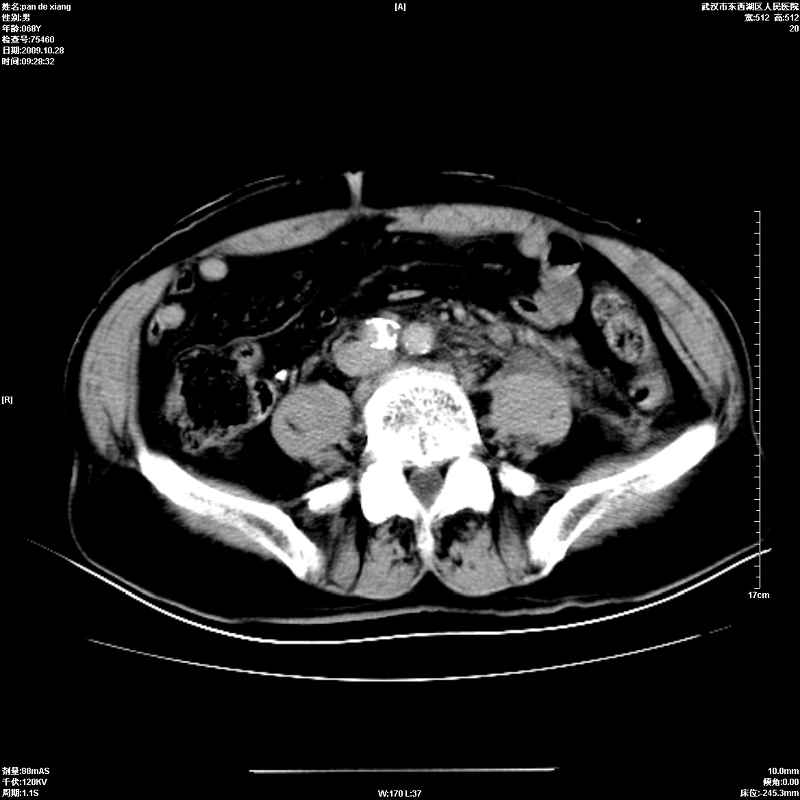

以下是引用杀毒软件在2009-10-28 20:41:00的发言:[br]结合临床考虑---白血病双肾改变或淋巴瘤。

以下是引用zxl51642在2009-10-29 9:59:00的发言:[br]结合临床“单克隆免疫球蛋白血症”,考虑双肾为继发损害并肾功能不全(尿中大量igg及少量iga、igm等大分子免疫球蛋白滤出所致继发损害),椎前软组织肿块为髓外造血。与浆细胞瘤有区别,平扫时有战友说的很清楚。